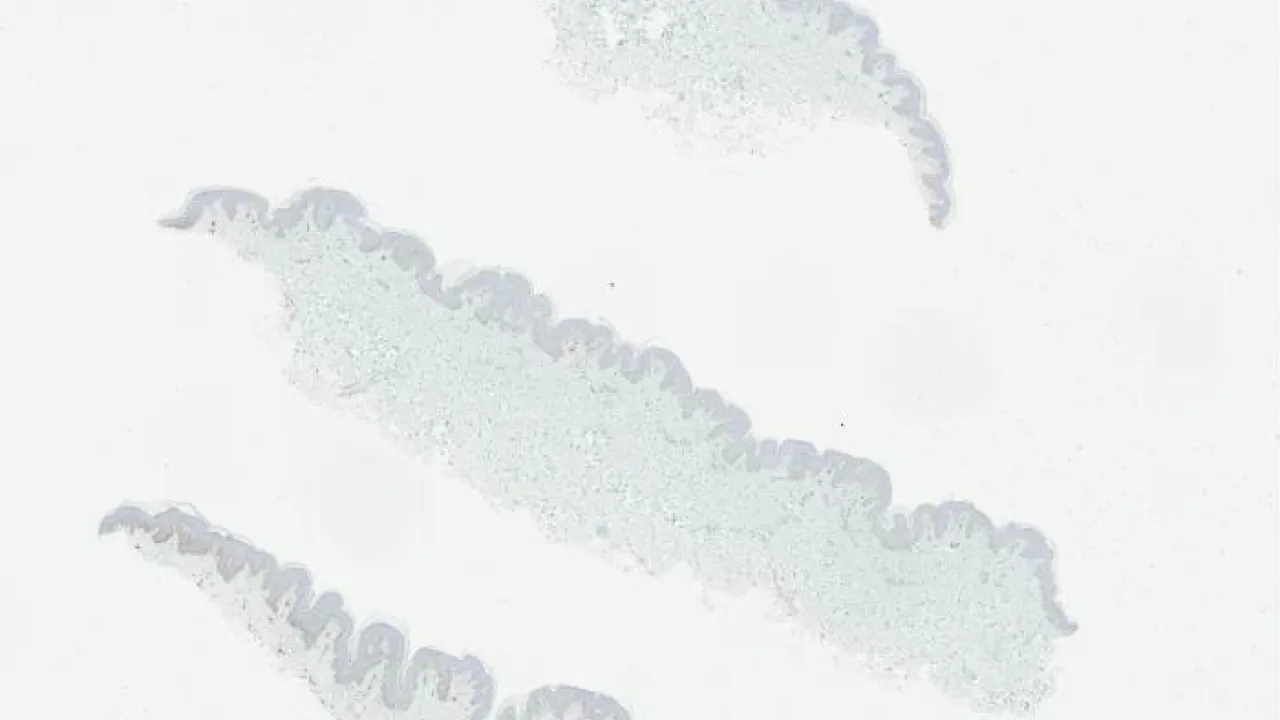

Ureter, Amyloidosis, Congo red stain